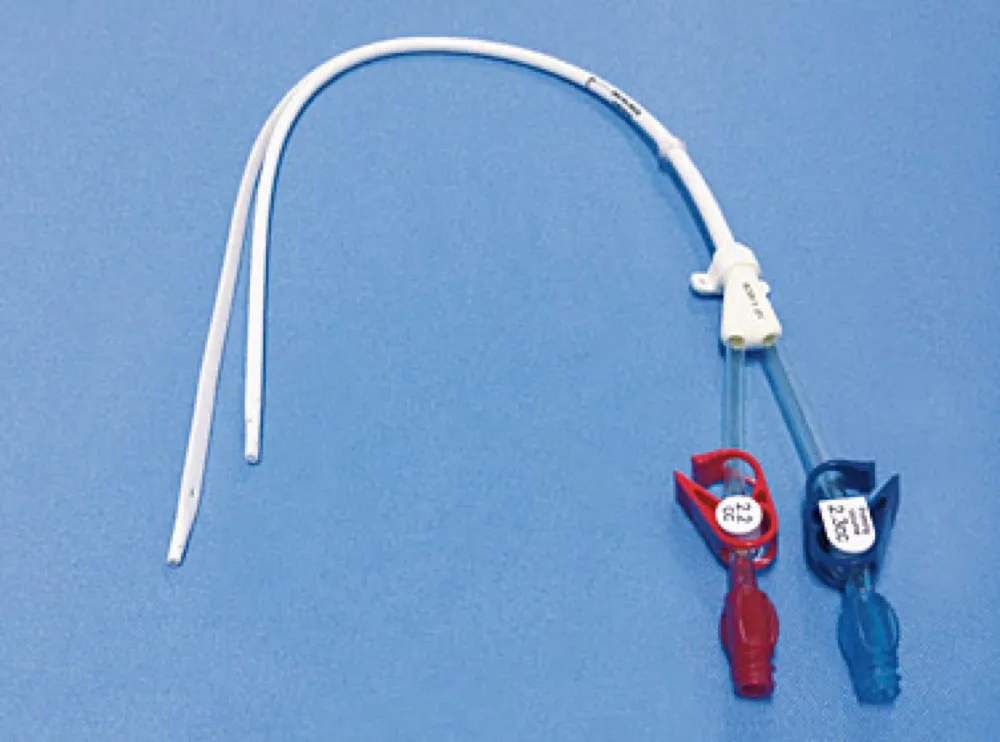

Hemodiafiltração exige ajuste de dose dos medicamentos? O que um caso de vancomicina pode nos ensinar

Hemodiafiltração exige ajuste de dose dos medicamentos? O que um caso de vancomicina pode nos ensinar

A hemodiafiltração pode aumentar significativamente a depuração de diversos medicamentos, levando a subdosagem quando usamos protocolos baseados em hemodiálise convencional. Entender a farmacocinética da droga e a prescrição da HDF é essencial para evitar falha terapêutica e ajustar corretamente as doses.